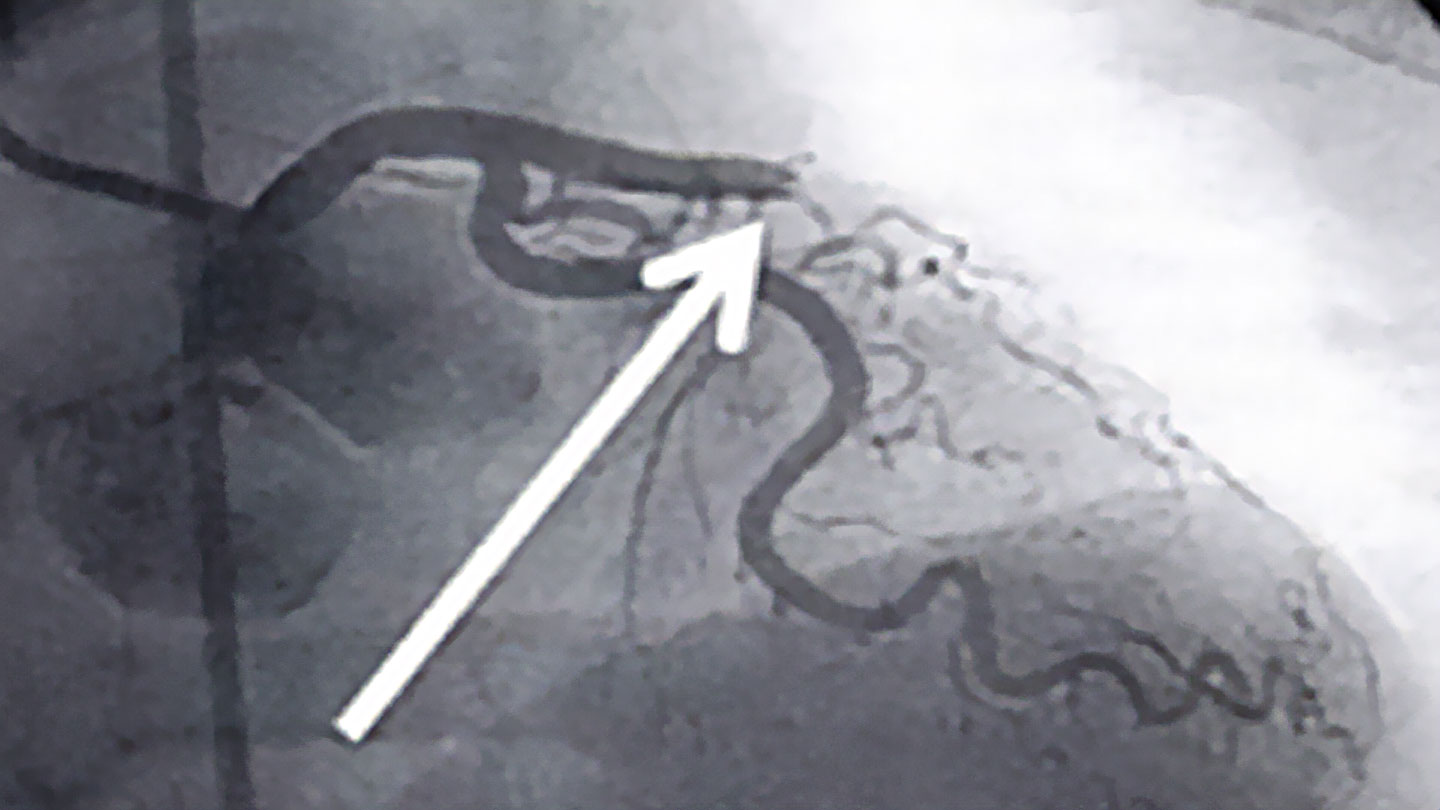

Bei einem Herzinfarkt zählt jede Sekunde. Je schneller ein verschlossenes Herzkranzgefäß wieder eröffnet wird, umso größer ist die Wahrscheinlichkeit, dass keine Spätfolgen wie zum Beispiel eine Herzschwäche oder Herzrhythmusstörungen zurückbleiben. Der Goldstandard in solchen Situationen ist die Durchführung einer Herzkatheteruntersuchung, mit der durch einen Ballon und der Platzierung einer Gefäßstütze (Stent) Herzkranzgefäße wieder durchgängig gemacht werden können. Somit bekommt der Herzmuskel wieder ausreichend Sauerstoff, um sich zu regenerieren.

© herzmedizin.berlin